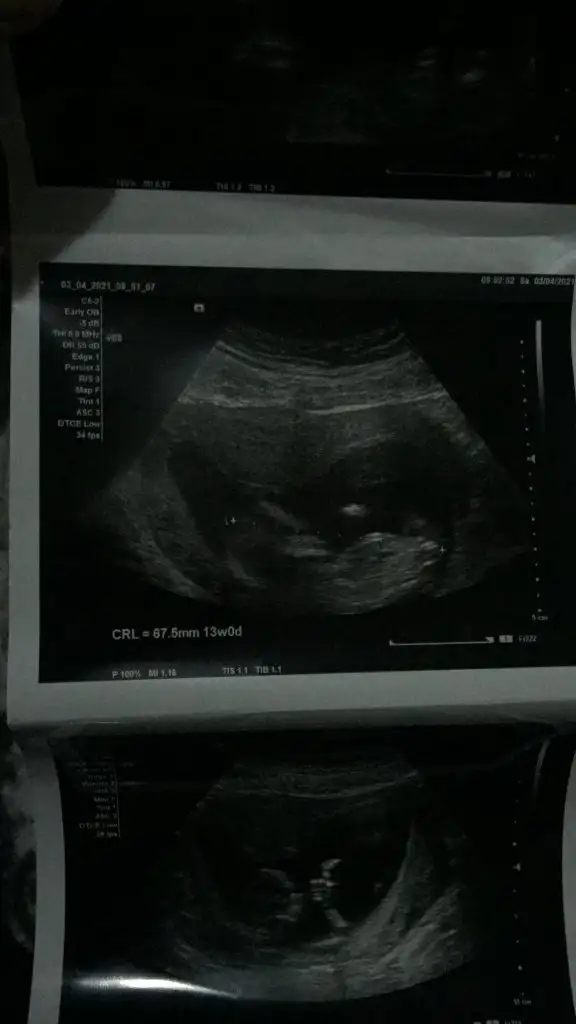

Merhaba. Rica etsem benim usmya tahmin yapar mısınız?

12+2 günlüktü burda. Karından detaylı ultrasondu.

Doktor benzetme yaptı ama kesin değil dedi.doktorla aynı olursa oyumu veririm

Eklentiler

• 6E497546-FA75-4DD1-81BC-3D41E934D3CE.webp

27,5 KB · Görüntüleme: 75